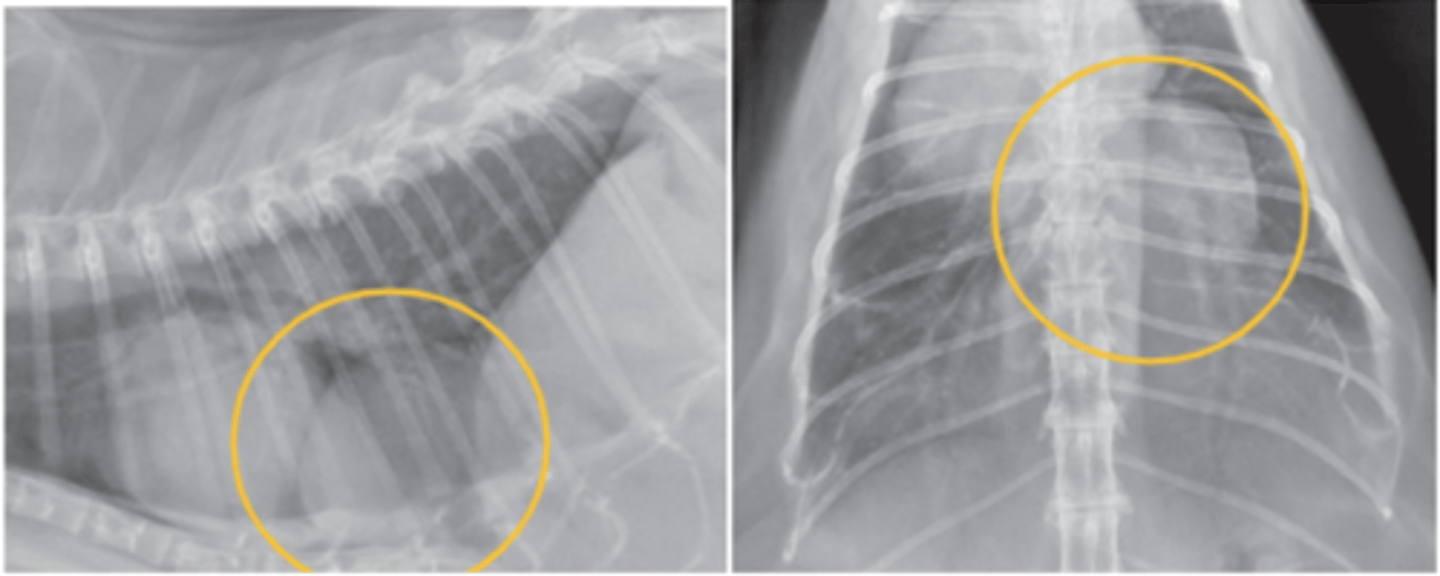

edema pulmonar

patología: